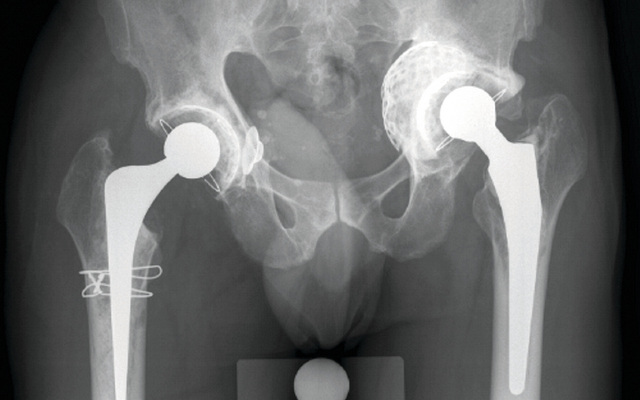

تمكن باحثون في معهد "فراونهوفر" في شتوتغارت بألمانيا من تطوير نوع جديد من الأوراك الاصطناعية، يتميز عن النوع التقليدي المستخدم حالياً في أنه يخلو من المعدن، ويضاهي العظام البشرية في مرونته.

وصنع الباحثون تجويف الورك من مركب بوليمري في غاية القوة ومقاوم للاهتراء. فيما صنعوا الرأس الفخذي من السيراميك. وإضافة إلى ذلك، فقد تم طلاء الأجزاء المواجهة للعظام بمادة هيدروكسيل الأباتيت لضمان اندماج النسيج العظمي بالبنية السطحية للورك المزروع.

وقالت جاسمين هيب، التي قادت فريق البحث: "إن الأوراك المصنوعة من الكروم والكوبالت والمستخدمة حالياً تفتقر إلى المرونة. وهي لا تنقل الثقل إلى العظام بالشكل الأمثل، ما يؤدي إلى احتمال تكيف العظام بصورة عكسية".

يذكر أن عمليات استبدال الورك تعد من أكثر العمليات شيوعاً في ألمانيا. إذ يقوم الأطباء الألمان بزراعة ما يقرب من 200 ألف ورك اصطناعي كل عام. وغالباً ما تحتاج الأوراك الاصطناعية إلى أن تستبدل بعد مرور عشر سنوات فقط.